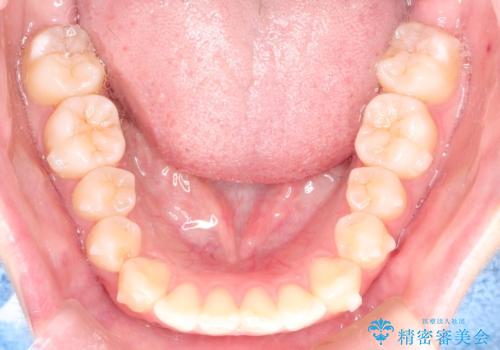

前歯のがたつきをインビザラインで目立たない矯正

- 上下の前歯のがたつきを主訴に来院されました。

マウスピースでの矯正を希望されたので、インビザラインで矯正治療を行うこととしました。

インビザラインではシュミレーションによりどのように歯が動くかを確認して矯正することができるので、患者様も安心して矯正をすることができました。